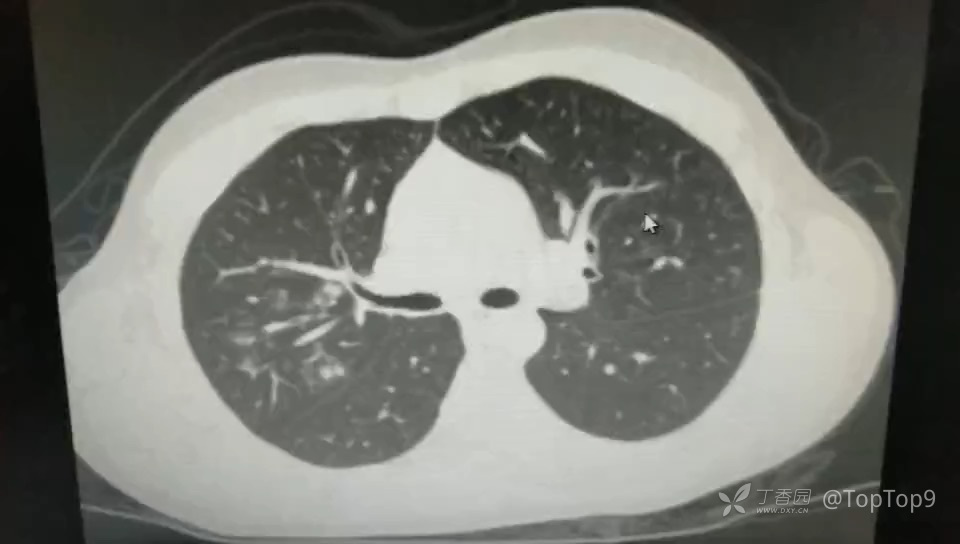

患者15岁学生,发热一天,最高38.1,有咳嗽,无其他症状。否认到过封控区。

因为本市出现新冠疫情,该患者就诊于发热门诊时被隔离。

请问,患者考虑什么问题?该做哪些化验检查?